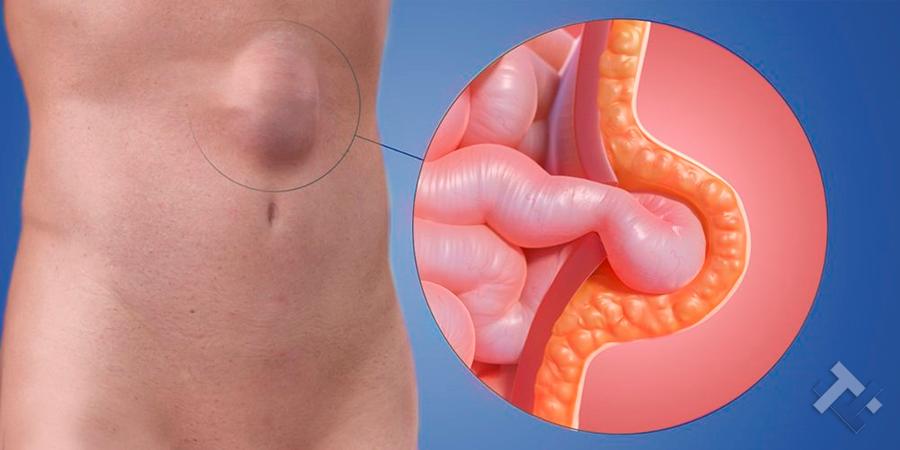

Κήλες - Κοιλιοκήλες:

Κήλες - Κοιλιοκήλες:

Ο Γενικός Χειρουργός Λιάγκος Γεώργιος MD PhD εκτελεί τις επεμβάσεις Λαπαροσκοπικά, Ενδοσκοπικά, Ανοιχτά Ελάχιστα Επεμβατικά και με Laser. Η θεραπεία εξατομικεύεται σε κάθε ασθενή ανάλογα με τις ανάγκες του. Αναλαμβάνει περιπτώσεις όπως κήλες και κοιλιοκήλες (αντιμετώπιση βουβωνοκήλης, αντιμετώπιση ομφαλοκήλης, θεραπεία επιγαστρικής κήλης, κήλη των αθλητών (Σύνδρομο κοιλιακών προσαγωγών), αντιμετώπιση μετεγχειρητικής κήλης, θεραπεία Μηροκήλης), πέτρες στη χοληδόχο κύστη, λαπαροσκοπική χολοκυστεκτομή, αντιμετώπιση Κύστη Κόκκυγος με λέιζερ (laser), παθήσεις πρωκτού, χειρουργική laser σύγχρονων κυκλικών ινών (αιμορροΐδες αντιμετώπιση, θεραπεία αιμορροϊδων με laser (LHP), αφαίρεση αιμορροΐδων με υπερήχους (HALL-RAR), χωρίς Χειρουργείο με ελαστικούς δακτυλίους (Τεχνική BARON-RBL), θεραπεία ραγάδας πρωκτού (Ραγάδα δακτυλίου), θεραπεία περιεδρικού συριγγίου, θεραπεία περιεδρικού αποστήματος, κονδυλώματα πρωκτού Θεραπεία, δερματικό ράκος (Skin tag) εκτομή, αντιμετώπιση Kνησμού, καρκίνος πρωκτού θεραπεία), παθήσεις Δέρματος, χειρουργική με laser CO2, αφαίρεση μορφωμάτων δέρματος - βιοψίες, αφαίρεση ελιάς (Σπίλου), σμηγματογόνος κύστης θεραπεία, αφαίρεση λιπώματος, είσφρυση όνυχος χειρουργείο, καρκίνος δέρματος θεραπεία, οξεία σκωληκοειδίτιδα, παθήσεις Λεπτού και Παχέος Εντέρου, ειλεός λεπτού εντέρου, εκκολπωμάτωση (Εκκολπωματίτιδα) σιγμοειδούς, καρκίνος παχέος εντέου, κολοστομίες, port χημειοθεραπείας κ.α.

Ο Γενικός Χειρουργός Λιάγκος Γεώργιος MD PhD εκτελεί τις επεμβάσεις Λαπαροσκοπικά, Ενδοσκοπικά, Ανοιχτά Ελάχιστα Επεμβατικά και με Laser. Η θεραπεία εξατομικεύεται σε κάθε ασθενή ανάλογα με τις ανάγκες του. Αναλαμβάνει περιπτώσεις όπως κήλες και κοιλιοκήλες (αντιμετώπιση βουβωνοκήλης, αντιμετώπιση ομφαλοκήλης, θεραπεία επιγαστρικής κήλης, κήλη των αθλητών (Σύνδρομο κοιλιακών προσαγωγών), αντιμετώπιση μετεγχειρητικής κήλης, θεραπεία Μηροκήλης), πέτρες στη χοληδόχο κύστη, λαπαροσκοπική χολοκυστεκτομή, αντιμετώπιση Κύστη Κόκκυγος με λέιζερ (laser), παθήσεις πρωκτού, χειρουργική laser σύγχρονων κυκλικών ινών (αιμορροΐδες αντιμετώπιση, θεραπεία αιμορροϊδων με laser (LHP), αφαίρεση αιμορροΐδων με υπερήχους (HALL-RAR), χωρίς Χειρουργείο με ελαστικούς δακτυλίους (Τεχνική BARON-RBL), θεραπεία ραγάδας πρωκτού (Ραγάδα δακτυλίου), θεραπεία περιεδρικού συριγγίου, θεραπεία περιεδρικού αποστήματος, κονδυλώματα πρωκτού Θεραπεία, δερματικό ράκος (Skin tag) εκτομή, αντιμετώπιση Kνησμού, καρκίνος πρωκτού θεραπεία), παθήσεις Δέρματος, χειρουργική με laser CO2, αφαίρεση μορφωμάτων δέρματος - βιοψίες, αφαίρεση ελιάς (Σπίλου), σμηγματογόνος κύστης θεραπεία, αφαίρεση λιπώματος, είσφρυση όνυχος χειρουργείο, καρκίνος δέρματος θεραπεία, οξεία σκωληκοειδίτιδα, παθήσεις Λεπτού και Παχέος Εντέρου, ειλεός λεπτού εντέρου, εκκολπωμάτωση (Εκκολπωματίτιδα) σιγμοειδούς, καρκίνος παχέος εντέου, κολοστομίες, port χημειοθεραπείας κ.α.